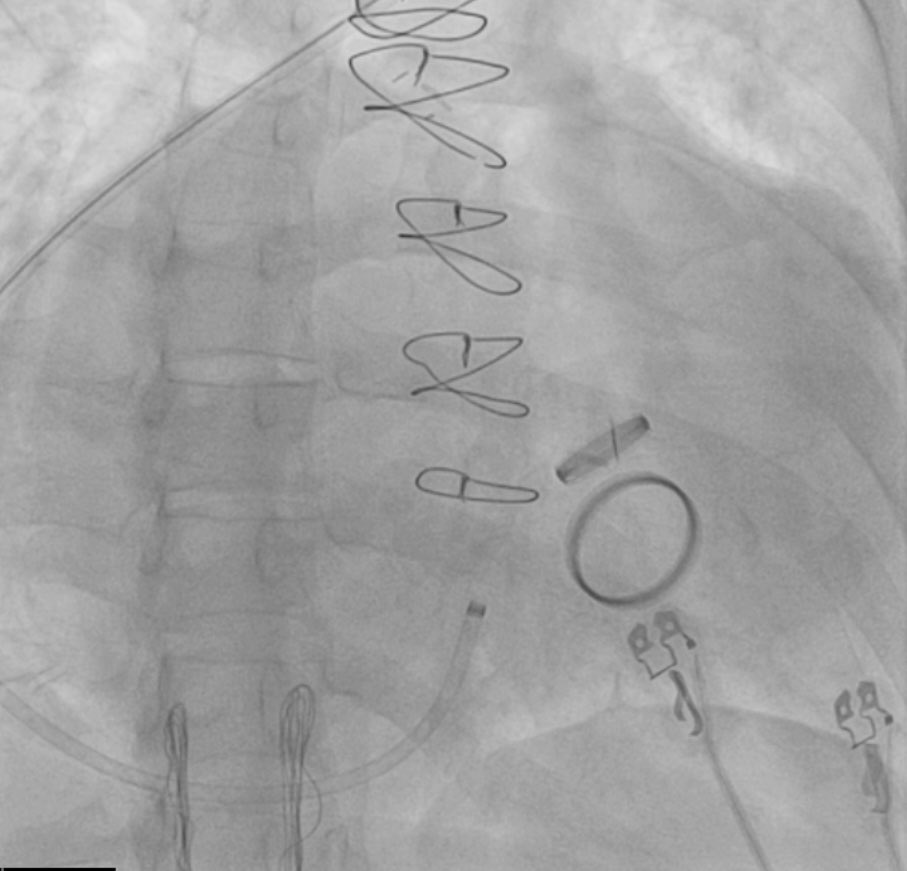

Is #PulseFieldAblation replacing RF Ablation?

Dr. Kristopher Heinzman & @pkothapalliMD explore its clinical promise, training risks & how EPs decide which patients fit PFA vs RFA.